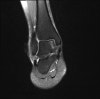

MRI : 거골의 박리성 골연골염(Osteochondral lesion of talus)